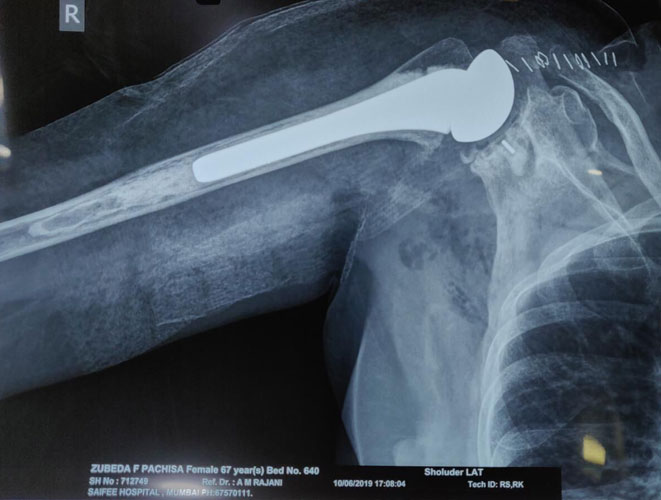

Post Shoulder Replacement Surgery X-Ray for Arthritis